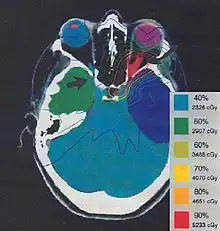

Typically, medical imaging is used to form a virtual patient for a computer-aided design procedure. A CT scan is often the primary image set for treatment planning while magnetic resonance imaging provides excellent secondary image set for soft tissue contouring. Positron emission tomography is less commonly used and reserved for cases where specific uptake studies can enhance planning target volume delineation.[9] Modern treatment planning systems provide tools for multimodality image matching, also known as image coregistration or fusion. Treatment simulations are used to plan the geometric, radiological, and dosimetric aspects of the therapy using radiation transport simulations and optimization. For intensity modulated radiation therapy (IMRT), this process involves selecting the appropriate beam type (which may include photons, electrons and protons), energy (e.g. 6, 18 megaelectronvolt (MeV) photons) and physical arrangements. In brachytherapy planning involves selecting the appropriate catheter positions and source dwell times [10][11] (in HDR brachytherapy) or seed positions (in LDR brachytherapy).

The more formal optimization process is typically referred to as forward planning and inverse planning.[12][13] Plans are often assessed with the aid of dose-volume histograms, allowing the clinician to evaluate the uniformity of the dose to the diseased tissue (tumor) and sparing of healthy structures.